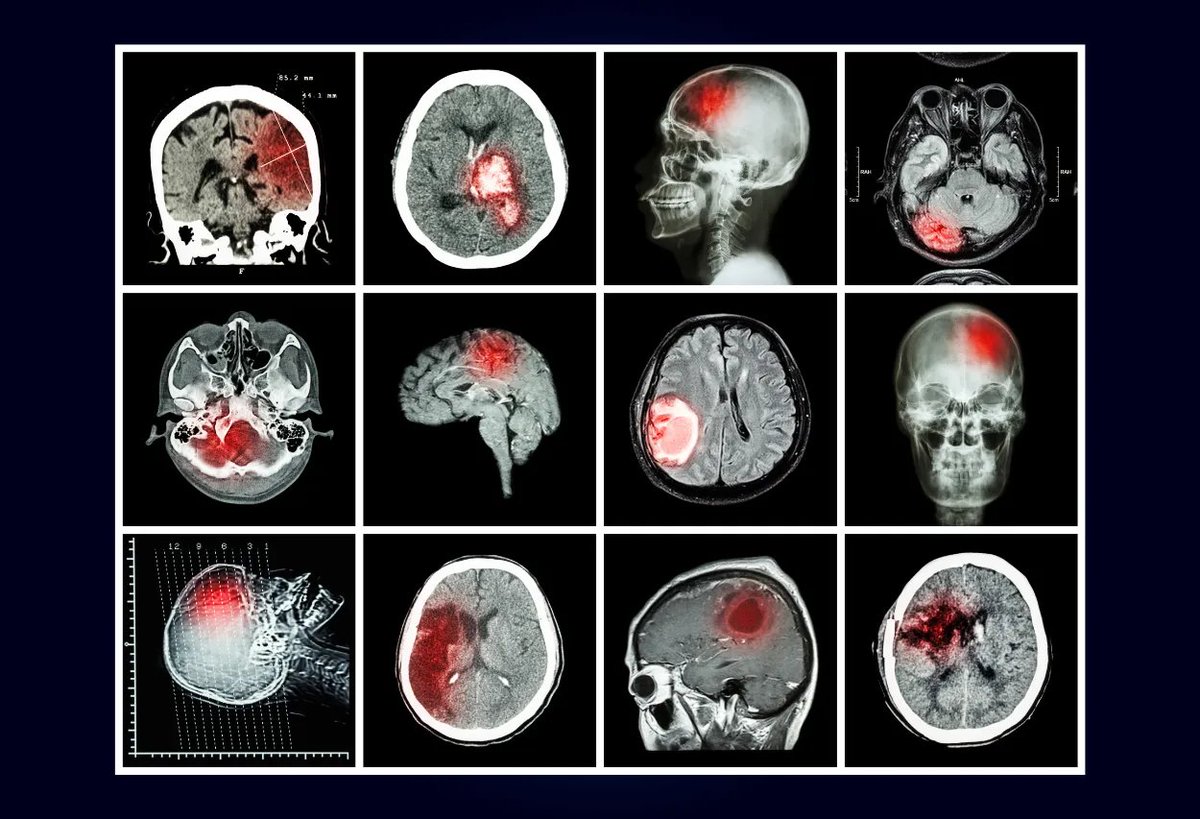

Mechanism 1 — Vaccines can cause chronic brain inflammation.

Brain inflammation and enlarged brains have been repeatedly linked to autism.

And this brain inflammation happens at a critical period of brain development.

Scientists have found that in children with autism:

• Inflammatory chemicals like IL-1β, IL-6, and IL-8 are elevated

• Their brains are often enlarged—a sign of swelling

• Their blood-brain barrier and gut barrier are leaky

• And aluminum—a known neurotoxin—is often found at sky-high levels inside their brains

One study even found aluminum levels in autistic brain tissue that were higher than almost any human brain tissue ever recorded.Image